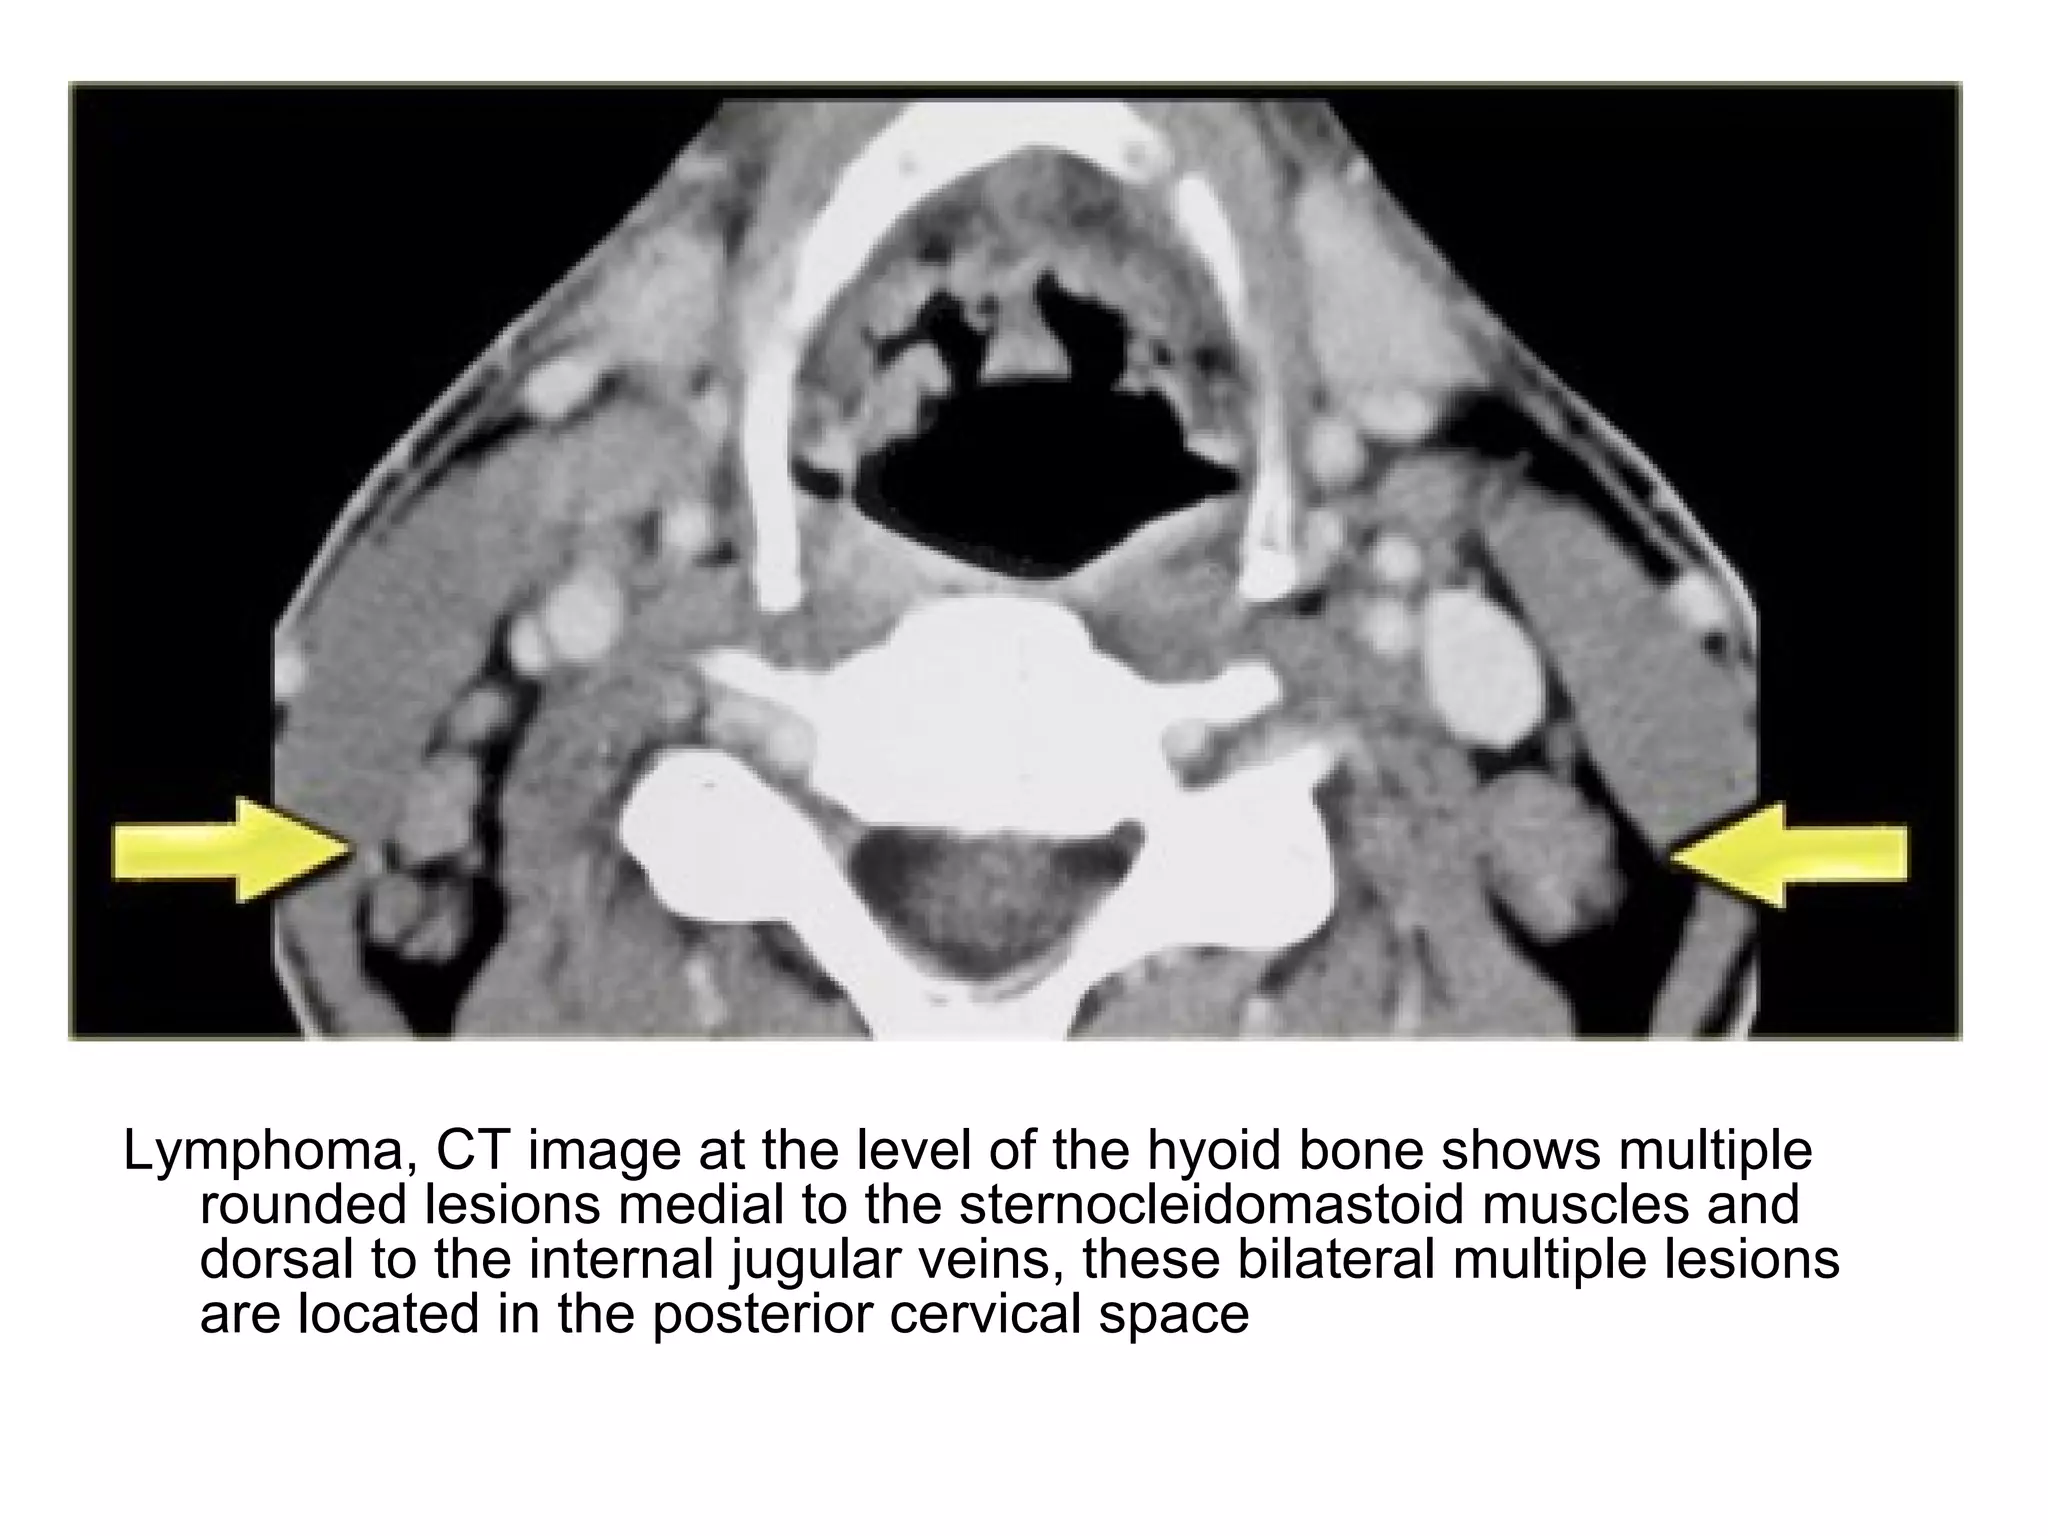

Lymphoma, CT image at the level of the hyoid bone shows multiple

rounded lesions medial to the sternocleidomastoid muscles and

dorsal to the internal jugular veins, these bilateral multiple lesions

are located in the posterior cervical space

Lymphoma, CT imageat the level of the hyoid bone shows multiple rounded lesions medial to the sternocleidomastoid muscles and dorsal to the internal jugular veins, these bilateral multiple lesions are located in the posterior cervical space